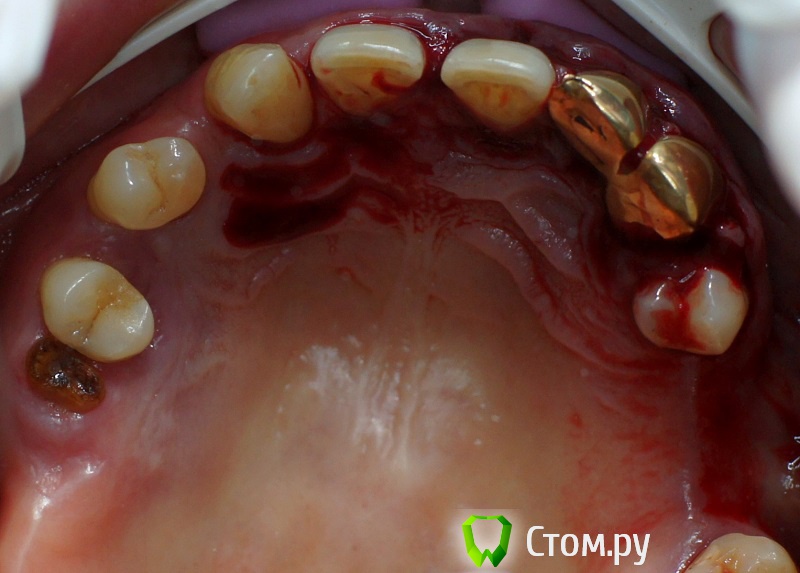

rin3225 Опубликовано 8 октября, 2014 Поделиться Опубликовано 8 октября, 2014 У пациента было желание сделать красивые зубы и улыбку!Проблема заключалась в массивной верхней челюсти , глубоком перекрытии и пациент не мог уйти без зубов! Отлив модели и выставив в центральную окклюзию было понятно, что без удаления всех зубов и поднятия прикуса с данной проблемой вопрос не решится. Обговорив все нюансы с пациентом,и получив согласие, было запланировано. заранее изготовлены акриловые протезы, предложено удаление всех зубов с одномоментной установкой имплантатов, внутриротавая сварка для первичной стабильности имплантатов и немедленная нагрузка 16 Ссылка на комментарий

ILGAMSA Опубликовано 8 октября, 2014 Поделиться Опубликовано 8 октября, 2014 А я бы фронт внизу оставил. Работу только сделана?Тогда ждем фото и Рентгены через полгода, год. 5 Ссылка на комментарий

rin3225 Опубликовано 8 октября, 2014 Автор Поделиться Опубликовано 8 октября, 2014 А я бы фронт внизу оставил. Работу только сделана?Тогда ждем фото и Рентгены через полгода, год. А я бы фронт внизу оставил. Работу только сделана?Тогда ждем фото и Рентгены через полгода, год.Была такая мысль изночально, но эстетики не будет при протезировании Ссылка на комментарий

Дмитрий Никитюк Опубликовано 8 октября, 2014 Поделиться Опубликовано 8 октября, 2014 С двух сторон синус + удаление, первичная фиксация импантов 2/4 имплантата + прикус , какой прогноз? Да, и нижний фронт оставил бы. Для синусов показаний не вижу. Но даже если бы их и нужно было делать, ограничился бы установкой 4-6 имплантатов, на которые одел бы 10-12 несъёмных зубов. Ссылка на комментарий